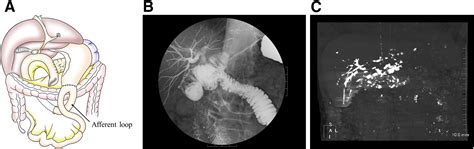

A Barium Swallow Exam is a specialized X-ray procedure that allows doctors to visualize the pharynx and the esophagus. During the test, the patient swallows a liquid containing barium sulfate, a chalky, metallic-tasting substance. Because barium is a contrast agent, it shows up white on X-ray images, effectively coating the lining of the throat and esophagus. This allows radiologists to identify anatomical abnormalities, such as strictures, tumors, hiatal hernias, or blockages, that might not be visible on standard X-rays.

The procedure is particularly useful for diagnosing conditions related to dysphagia (difficulty swallowing) or gastroesophageal reflux disease (GERD). By watching the liquid move through the esophagus in real-time, the radiologist can observe how well the muscles are functioning and whether the passage is clear.